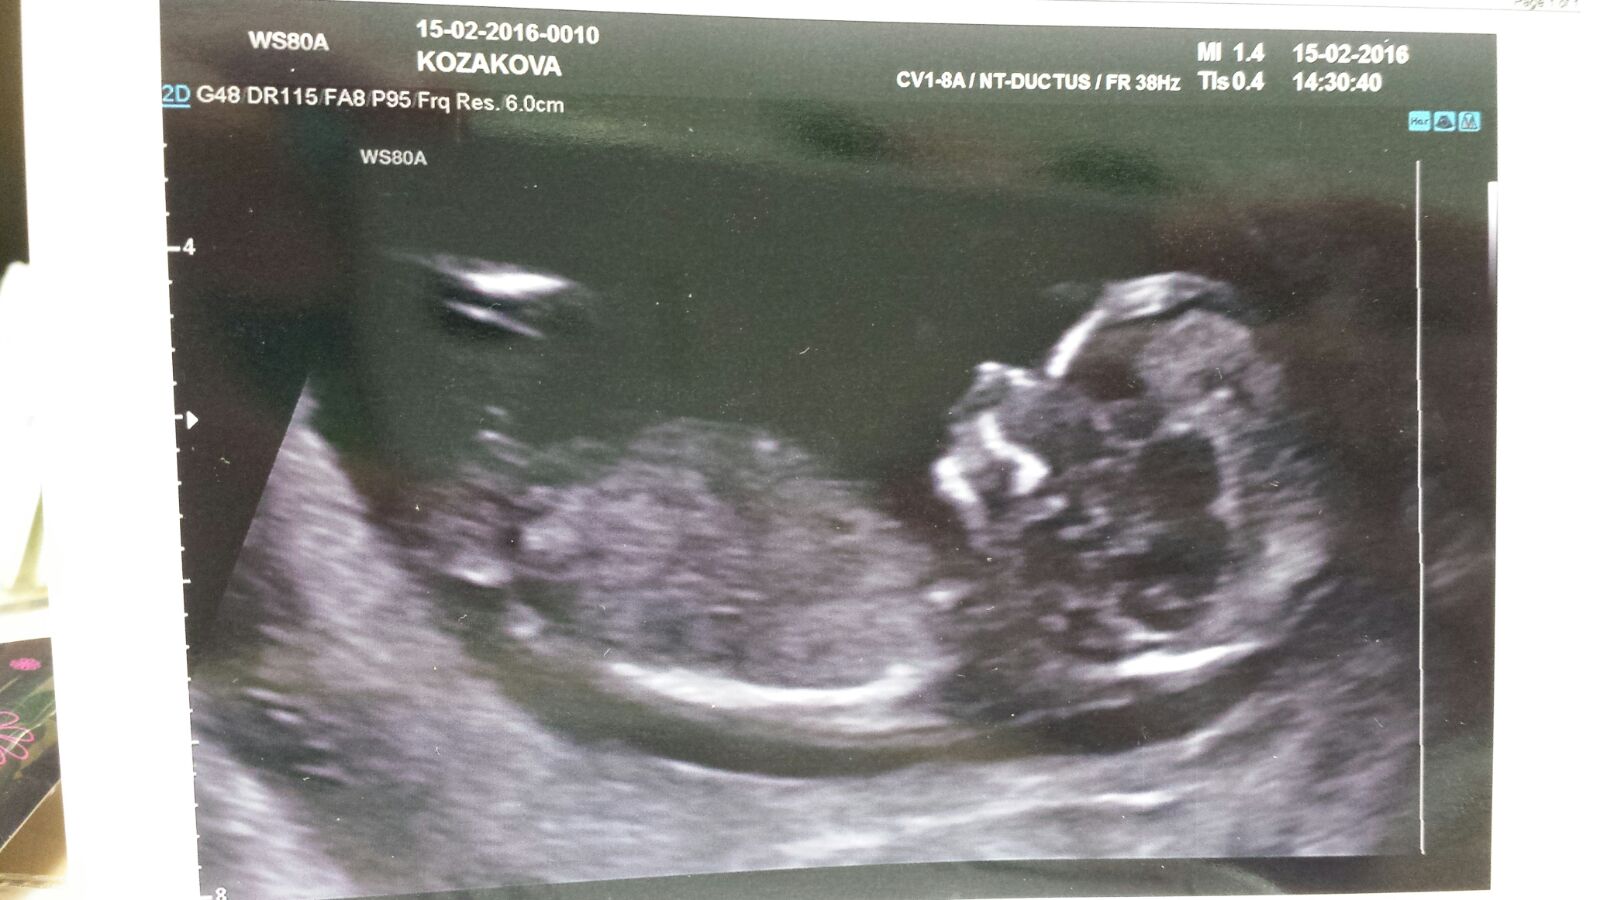

Holky moc vam dekuji :* jj rekli 🙂 holka se nam ukazala 🙂 a pan dr byl opravu sikovny 🙂

Zdravím maminku, koukám, že jsme se málem potkaly na screeningu 😊 jinak gratuluji...